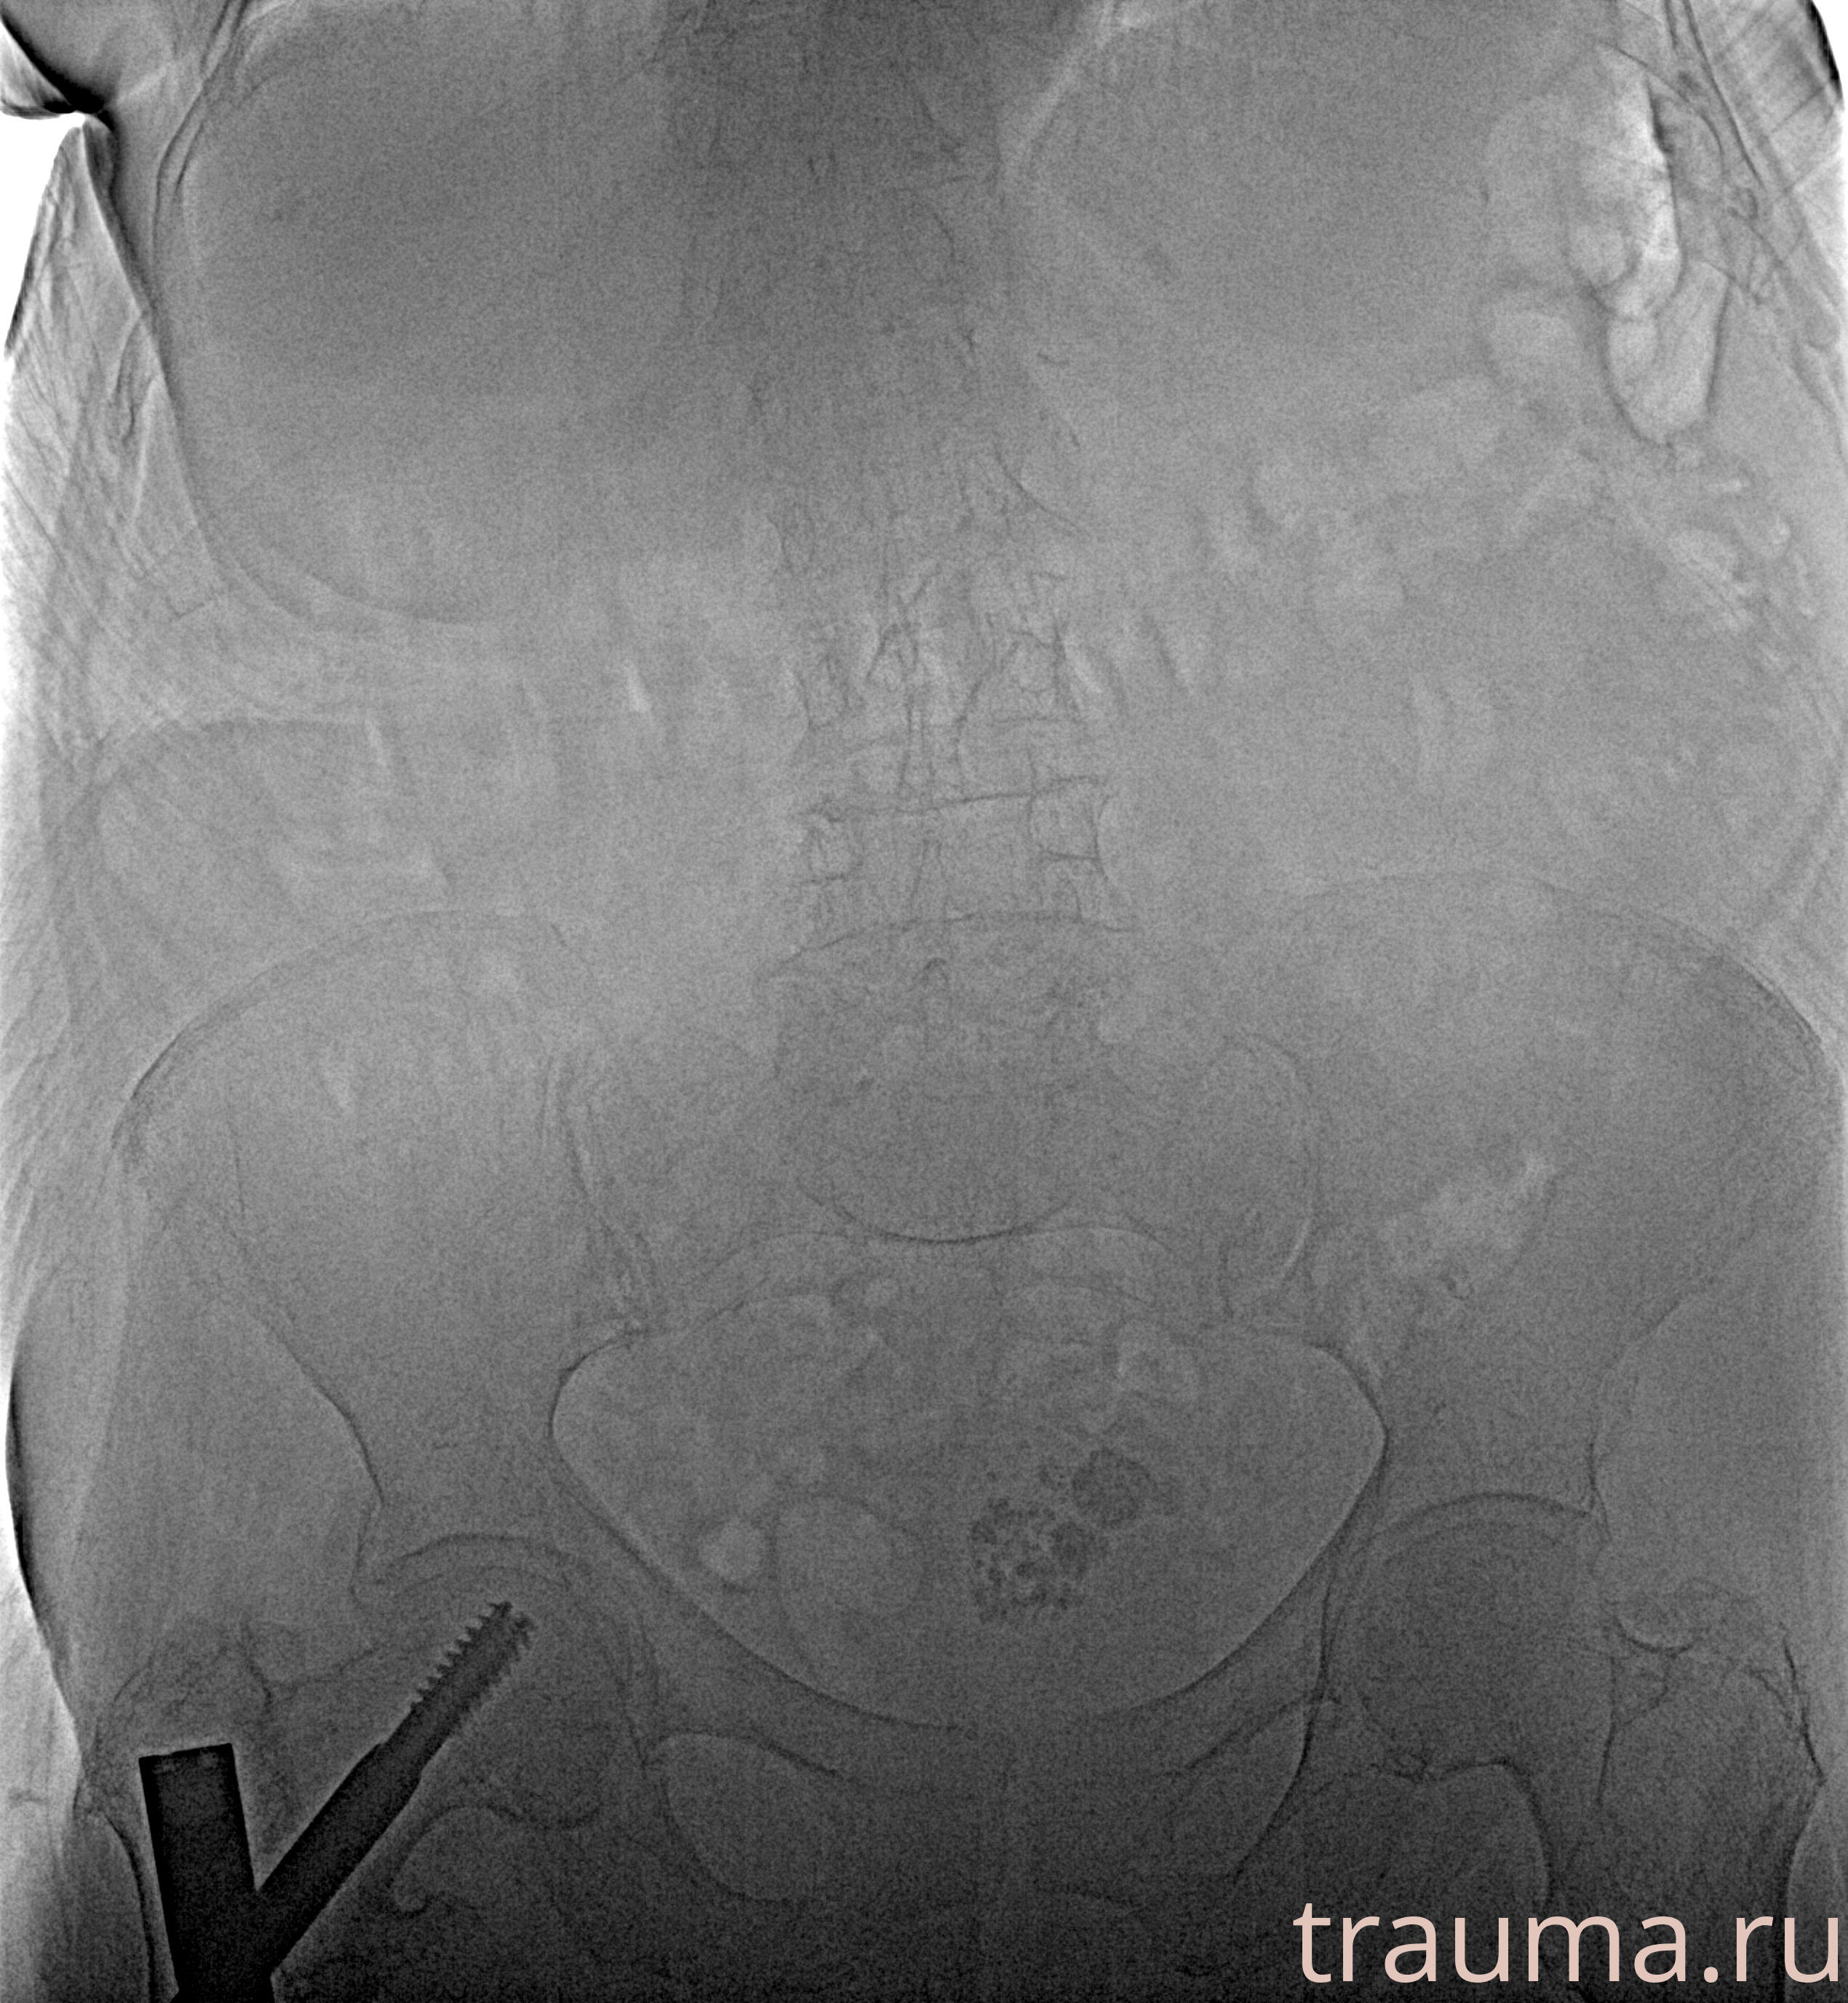

Рентгенограммы

Рентген на дому: по вашему адресу приезжает врач-рентгенолог, травматолог-ортопед с мобильным рентгеновским аппаратом, проводит диагностику травмы или заболевания, делает необходимые рентгенограммы, дает рекомендации по дальнейшему лечению. Получить качественные снимки в домашних условиях возможно благодаря уникальной методике, разработанной МосРентген Центром для института  Склифосовского